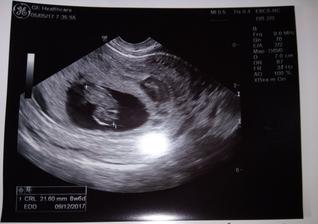

5.5.2017 - druhá kontrola, máme srdíčko a první fotečku 🙂